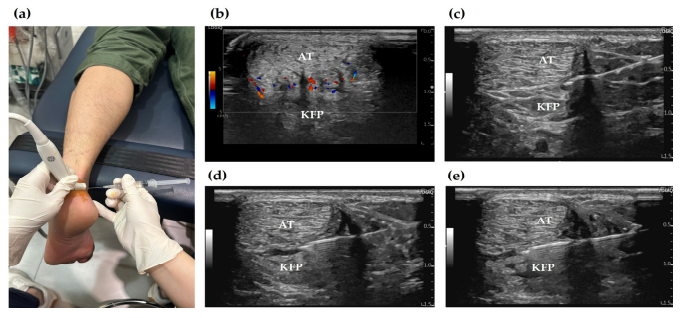

만성 건병증 부위에는 저산소 상태를 보상하기 위해 병적인 ‘신생 혈관’이 자라나는데, 이 신생 혈관을 따라 감각 신경 섬유도 함께 침투합니다. 이것이 지속적인 통증(신경성 염증)의 원인이 되죠

이럴 때, 초음파를 보면서 염증이 있는 부위에 고용량 약침을 주사해서 치료합니다.

PDRN 연아 약침, 태반 자하거 약침은 염증을 완화하고 조직 재생까지 돕습니다. > 4단계: 힘줄(tendon, 건)의 회복 > > 재생유도-Remodeling 마지막 단계는 아킬레스건이 뼈에 붙는 부위 즉, 건 부착부를 자극하여 건 자체의 퇴행을 회복시키는 단계입니다.

하지만 12회 치료 후 컬러 도플러 초음파상에서 병변 부위의 신생 혈관 신호가 현저히 감소한 것이확인되었습니다.**